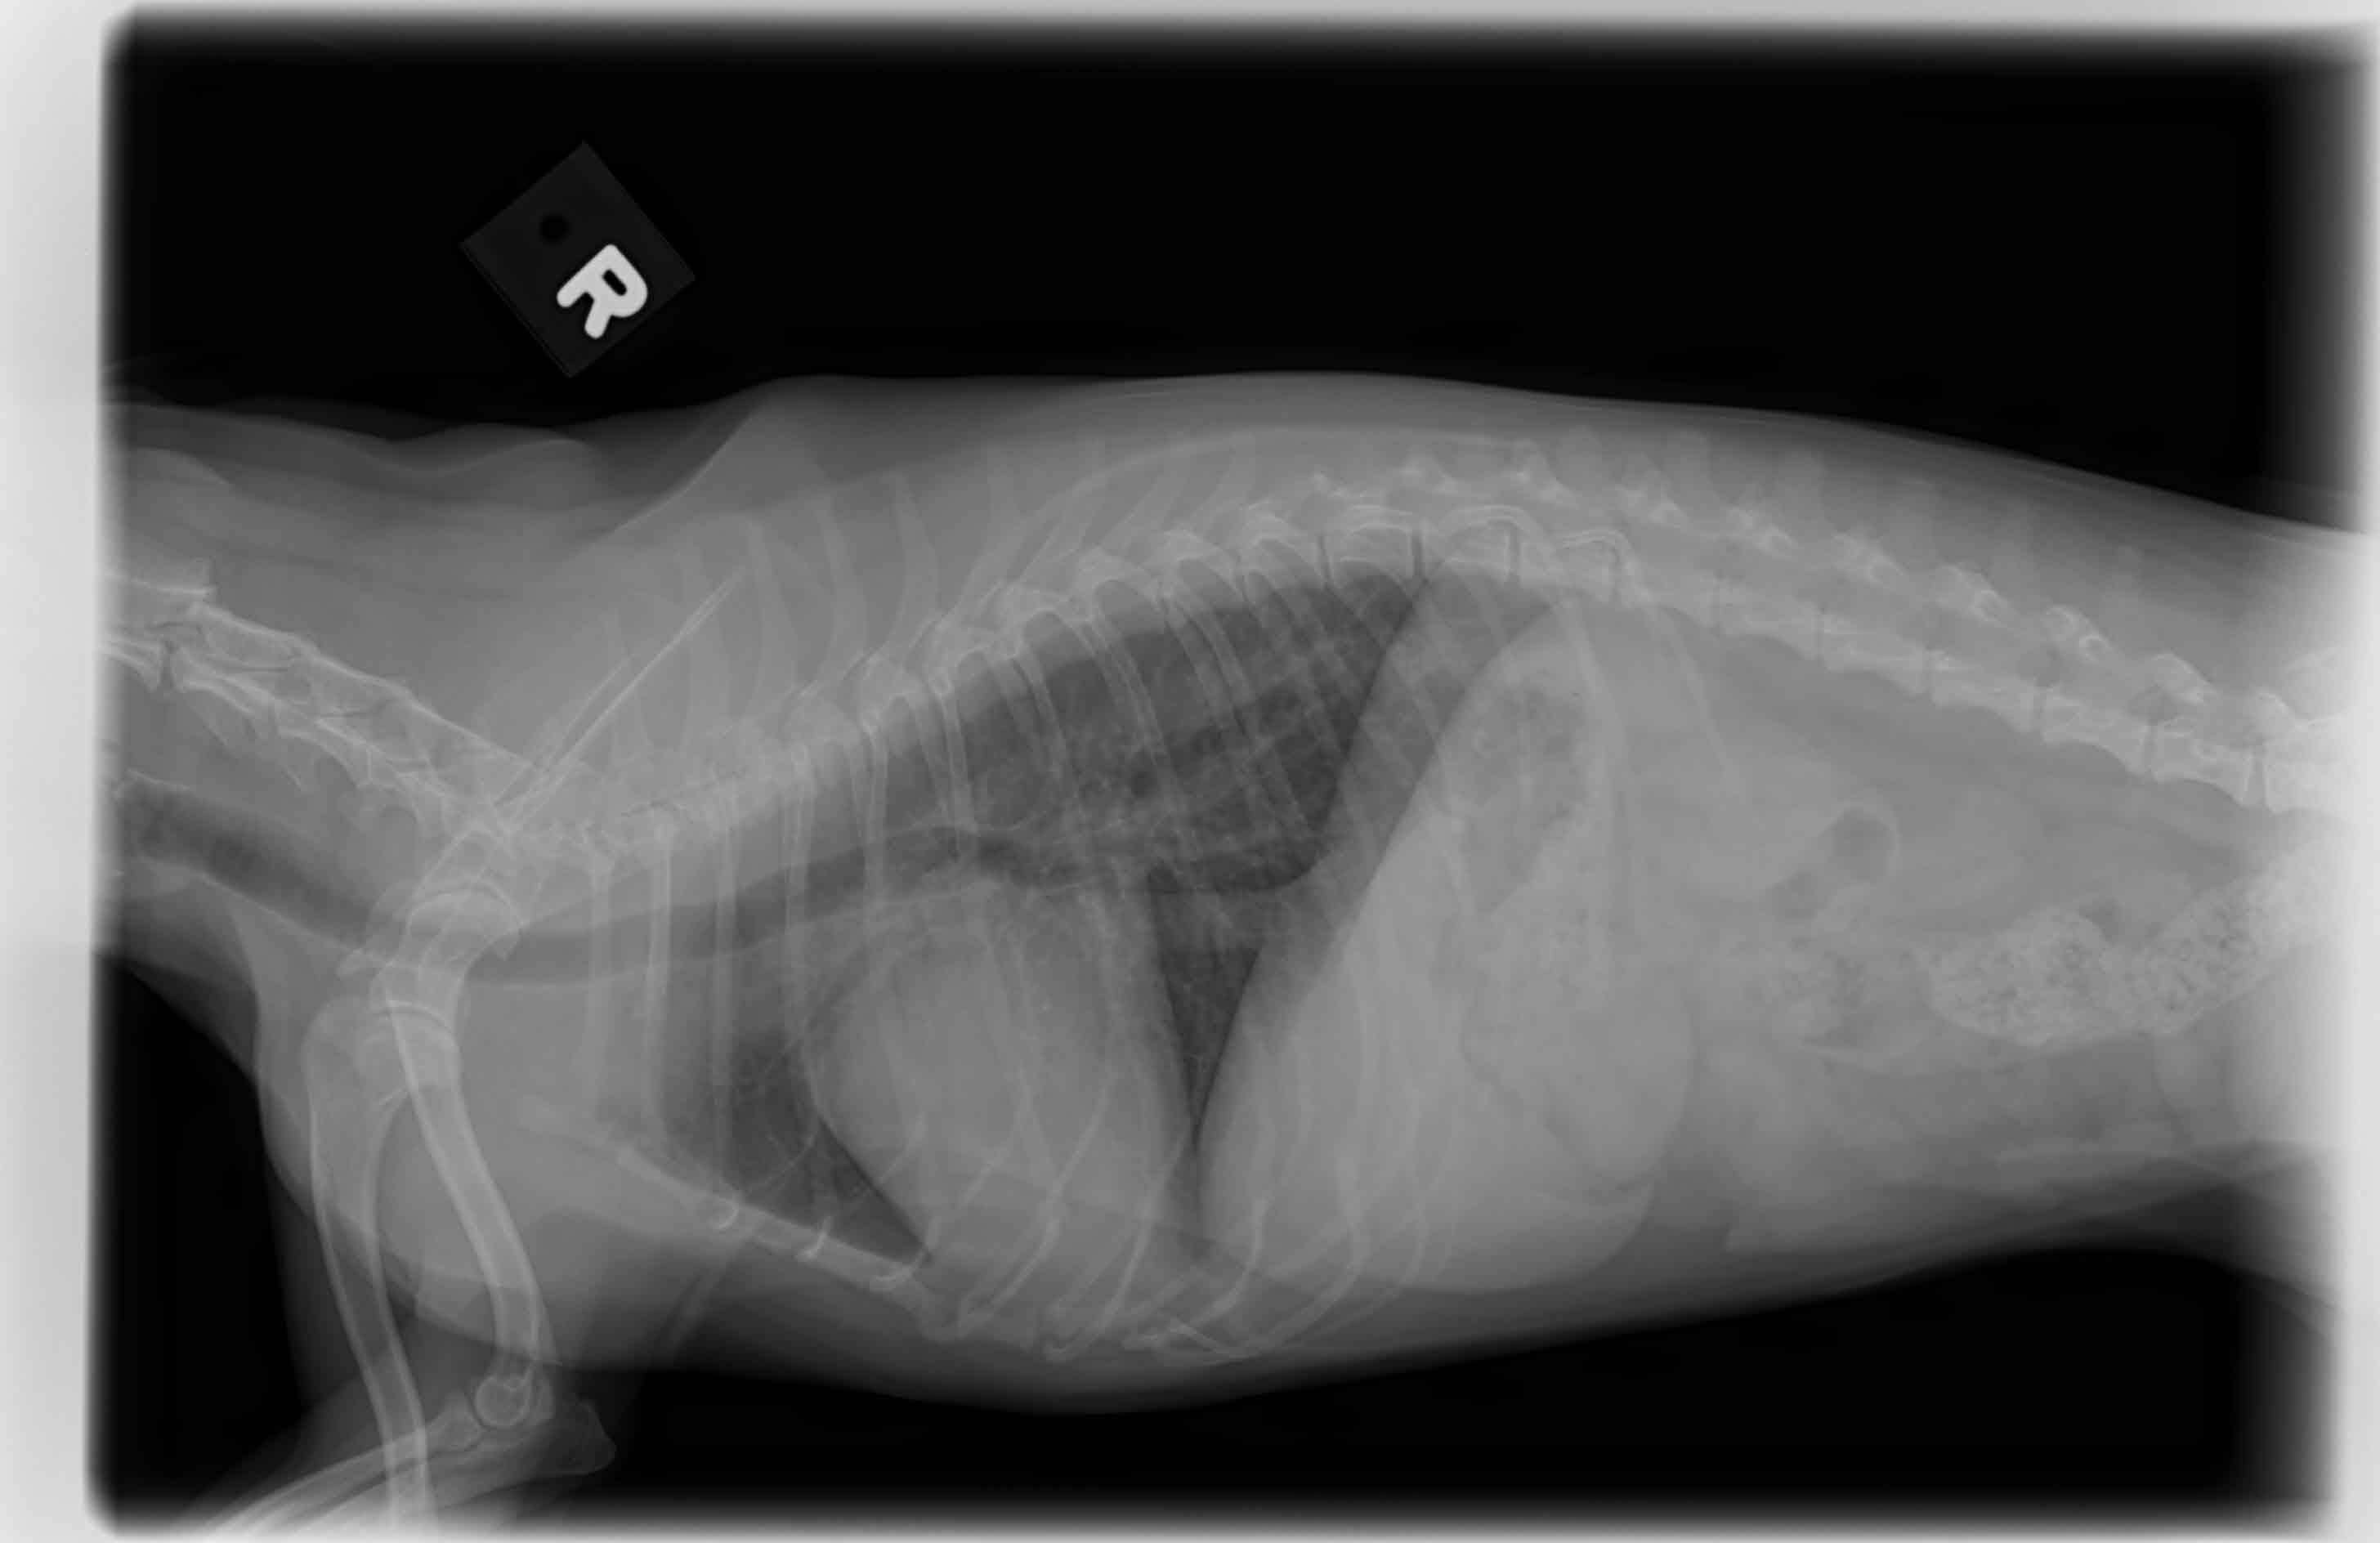

my dog had an upset stomach from people food. took her too a new vet. Told me very "severe heart murmor". I was scared, i had been feeding her Rachel ray which may be linked to enlarged heart. tests and x-ray (didn't see cardiologist yet) and they say her heart is enlarged. Not enough space to explain but they seem a little $$ hungry, scaring me into tons of stuff. is this 12 year old chihuahua heart SEVERELY enlarged? They made it sound extremely enlarged and crazy murmor.

The heart does indeed appear to be enlarged and the trachea (windpipe) pushed up by the heart which can cause discomfort and coughing. Murmurs and valve disease are quite common in chihuahuas (diet related dilated cardiomyopathy is generally associated with a milder murmur and larger heart). An ultrasound exam to assess the valves and the strength and thickness of the heart muscle or review from a cardiologist is recommended in order to determine the underlying issues as treatment to manage and reduce the symptoms are very different depending on the type of heart condition which is predominant